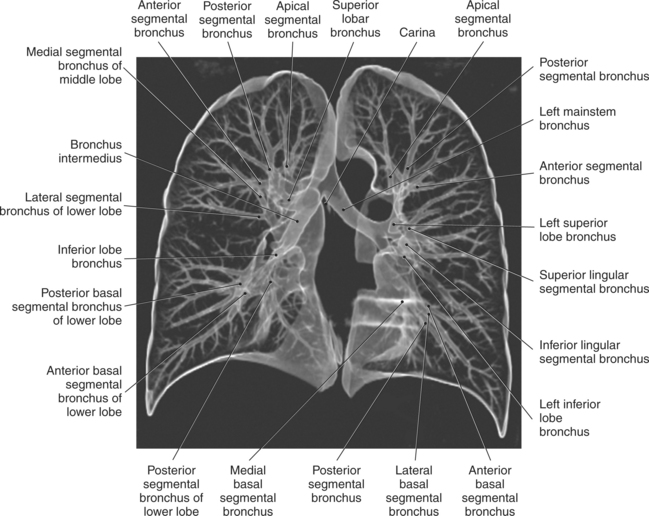

The trachea bifurcates into the left and right mainstem (primary) bronchi at approximately the level of T5. This location is commonly referred to as the carina (Figure 6.9). The right main bronchus is wider, shorter, and more vertical in orientation then the left. At the hilum the mainstem bronchi enter the lung and divide into secondary or lobar bronchi. Secondary bronchi correspond to the lobes of the lungs, thus with three divisions on the right (superior, middle, inferior) and two divisions on the left (superior and inferior) (Figure 6.9, and 6.18 through 6.20). There is further division of the secondary bronchi into tertiary or segmental bronchi that extend into each segment of the lobes (bronchopulmonary segments) (Figure 6.21 and Table 6.1). There are typically 10 segments within each lung. Each bronchopulmonary segment is functionally independent and can be individually removed surgically. The bronchial tree continues to divide many times into smaller bronchi, then into bronchioles (Figure 6.22). Each bronchiole continues to divide until it reaches the terminal end as alveoli, which are the functional units of the respiratory system. Gaseous exchange between alveolar air and capillary blood occurs through the wall of the alveoli.

TABLE 6-1

| LOBE | RIGHT LUNG | LEFT LUNG |

| Superior lobe | Apical segment Posterior segment Anterior segment |

Apical segment Posterior segment Anterior segment Superior lingular segment Inferior lingular segment |

| Middle lobe | Lateral segment Medial segment |

|

| Inferior lobe | Superior segment Medial basal segment Anterior basal segment Lateral basal segment Posterior basal segment |

Superior (apical) segment Medial basal segment Anterior basal segment Lateral basal segment Posterior basal segment |